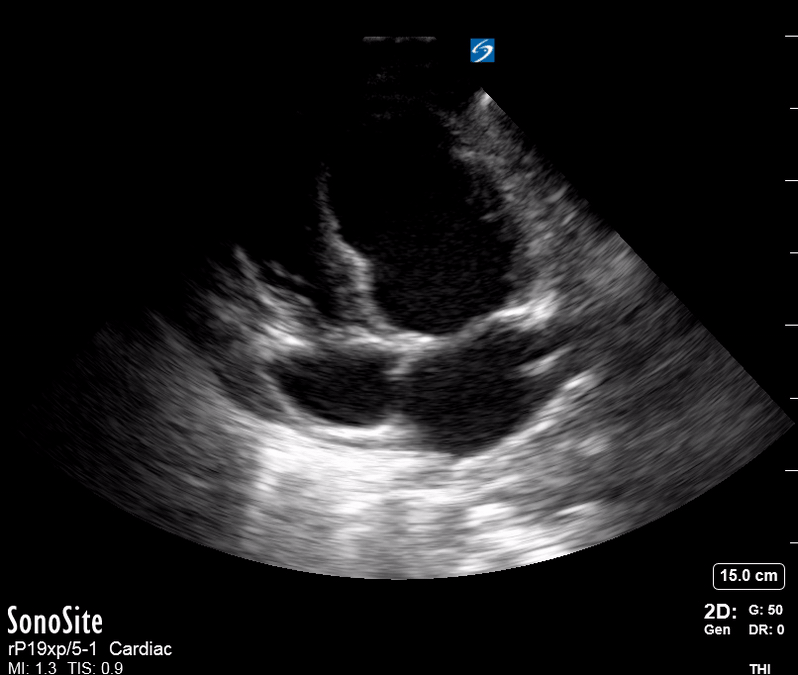

Ejection: is the LV dilated or significantly impaired?

THE VIEWS

The PLAX view is versatile and allows the recognition of multiple landmarks, making it good for visual estimation of LV contractility. It is essential to optimize the view ensuring a true sagittal long axis, as being oblique to the LV chamber may underestimate its size and overestimate its emptying. The PSAX view at the level of the papillary muscles reveals the entire muscular circumference and concentric squeeze of the LV. It is useful to estimate both global function and focal wall motion abnormalities. The A4C view, although technically challenging, provides good insight into the global myocardial function and chamber size.

LV CONTRACTILITY

Qualitative assessment of the LV and visual estimation of Ejection Fraction is based on three parameters:

Endocardial excursion.

Myocardial thickening.

Movement of the anterior leaflet of the mitral valve.

A qualitative assessment is typically categorised as:

Normal (LVEF 50-65%)

Moderately Depressed (LVEF 30-50%)

Severely Depressed (LVEF < 30%)

Hyperdynamic (LVEF > 65%)

SIGNIFICANTLY IMPAIRED / DILATED LV

A severely depressed LV contractility, particularly when paired with a plethoric IVC or lung B-lines, indicates systolic heart failure. Chronically raised afterload can lead to severe dilation of the LV.

A “non-coordinated myocardial activity” can be recognised during cardiac arrest, and its prognosis is beyond poor.

HYPERDYNAMIC

In contrast, hyperdynamic states are associated with decreased afterload and are classically found in patients with sepsis or severe hypovolaemia. A hyperdynamic heart should be accompanied by a small, collapsing IVC. Moreover, is essential to remember that tachycardic is not the same as hyperdynamic, as the latter is a measure of contractile activity and emptying. A tachycardic heart is not necessarily hyperdynamic.

PITFALLS

While distinguishing normal function from severe dysfunction might be easy, moderate LV depression is more difficult to reliably discern. Also, it should be noted that even with a preserved ejection fraction, heart failure still remains a possible cause of dyspnea. A big percentage of heart failure cases have some component of impaired relaxation, leading to diastolic dysfunction, or heart failure with preserved ejection fraction.

E-POINT SEPTAL SEPARATION

Active movement of the MV anterior leaflet during diastole, so it nearly touches the septum, correlates with good LV filling and ejection fraction. This can be assessed objectively by measuring the E-point septal separation (EPSS), which is the distance between the septum and the mitral anterior leaflet either in B-mode or M-mode. EPSS < 7mm is considered normal. EPSS is a good surrogate measure of ejection fraction, but it should be used with caution, as septal hypertrophy and mitral valve stenosis can lead to wrong estimations. In the PLAX view, it is important to have the septum lying horizontally flat on the image, as an oblique orientation may result in an overestimation of the EPSS.